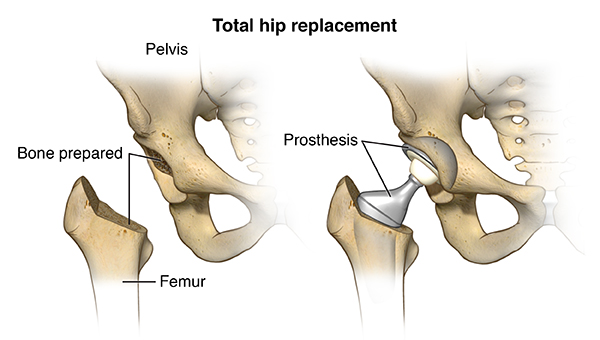

Hip replacement surgery, also known as total hip arthroplasty, is a highly effective procedure for individuals experiencing severe hip pain, stiffness, and limited mobility due to arthritis, injury, or degenerative joint conditions. The surgery replaces damaged bone and cartilage in the hip joint with high-quality prosthetic components made from metal, ceramic, or medical-grade plastics. These implants replicate the natural movement and function of a healthy hip, allowing patients to regain smooth, pain-free motion, whether through a total replacement (ball and socket) or partial replacement targeting the affected area.

The procedure begins with a comprehensive pre-surgical evaluation, including imaging studies, bone health assessment, and joint function analysis. During surgery, damaged areas of the hip are removed and replaced with customized implants designed for optimal stability and motion. Postoperative care focuses on early movement, guided physical therapy, and gradual strengthening of surrounding muscles. Most patients begin gentle exercises within a day or two, promoting circulation and preventing stiffness, while continuous monitoring by our orthopedic and rehabilitation team ensures proper healing and maximum recovery.

Hip replacements can be total (ball and socket) or partial (only the damaged portion replaced), depending on the patient’s condition and surgical recommendation.